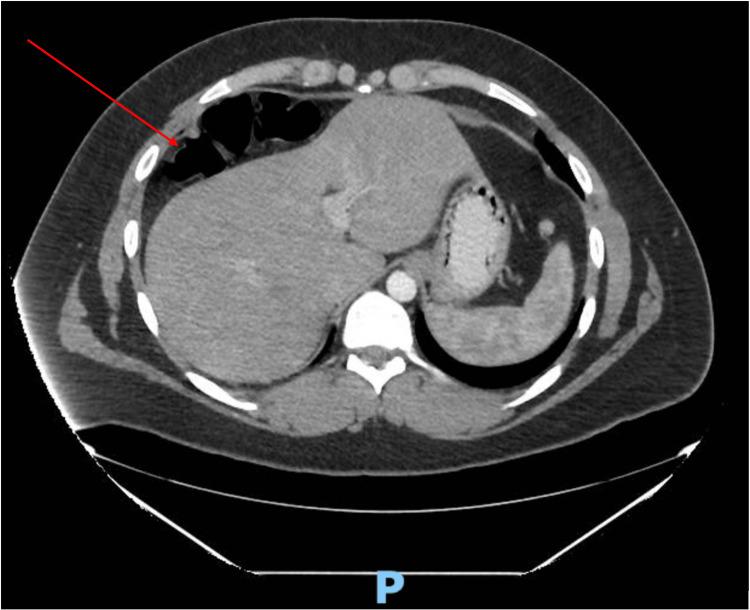

Chilaiditi's sign (colonic interposition) is a rare anomaly due to an abnormally located portion of the colon that is interposed in between the liver and the diaphragm. This rare anomaly is often incidentally seen on chest or abdominal radiographs. Chilaiditi's radiographic sign is usually asymptomatic, whereas the medical condition accompanied by clinical symptoms is termed Chilaiditi's syndrome. Possible causes of the syndrome include a long and mobile colon, scarring of the liver (cirrhosis), ascites, long-standing lung disease, as well as laxity of the falciform ligament. The most common clinical signs of Chilaiditi's syndrome include gastrointestinal symptoms; however, clinical presentation can vary. This report describes a case of a 21-year-old male patient who presented with a longstanding history of left upper quadrant epigastric abdominal pain with diarrhea (six to eight loose watery stools). The patient was diagnosed with Crohn's colitis and had tried a myriad of medical therapies with no adequate response. He chose to seek a second opinion and was subsequently discovered to have Chilaiditi's syndrome via computed tomography (CT) and confirmed by barium enema. The patient then elected to undergo a right laparoscopic colectomy to resolve the symptoms. By postoperative day five, all symptoms had resolved including abdominal pain and diarrhea. Therefore, it is important to consider Chilaiditi's syndrome as a differential diagnosis in persons presenting with left upper quadrant pain and symptoms of Crohn's colitis, especially those treated with adequate medical therapy without alleviation of symptoms.

奇莱迪蒂氏征(结肠间位)是一种罕见的异常情况,是由于结肠的异常位置部分夹在肝脏和膈肌之间。这种罕见的异常情况常在胸部或腹部X光片上偶然发现。奇莱迪蒂氏X光征通常无症状,而伴有临床症状的病症则称为奇莱迪蒂氏综合征。该综合征的可能病因包括结肠冗长且活动度大、肝脏瘢痕形成(肝硬化)、腹水、长期肺部疾病以及镰状韧带松弛。奇莱迪蒂氏综合征最常见临床体征包括胃肠道症状;然而,临床表现可能有所不同。本报告描述了一名21岁男性患者的病例,该患者有左上腹上腹部长期疼痛伴腹泻(每天六至八次稀水样便)的病史。该患者被诊断为克罗恩氏结肠炎,尝试了多种药物治疗但均无充分疗效。他选择寻求第二种意见,随后通过计算机断层扫描(CT)发现患有奇莱迪蒂氏综合征,并经钡剂灌肠证实。该患者随后选择接受右半结肠腹腔镜切除术以缓解症状。术后第五天,所有症状包括腹痛和腹泻均已缓解。因此,对于出现左上腹疼痛和克罗恩氏结肠炎症状的患者,尤其是那些接受了充分药物治疗但症状未缓解的患者,将奇莱迪蒂氏综合征作为鉴别诊断很重要。